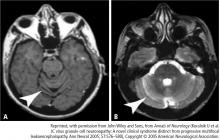

The relationship between congestive heart failure and frailty is complex. Not only does heart failure itself result in frailty, but its multiple therapies can put additional stress on a frail patient. In addition, the heart failure and its treatments can negatively affect coexisting disorders (Figure 1).